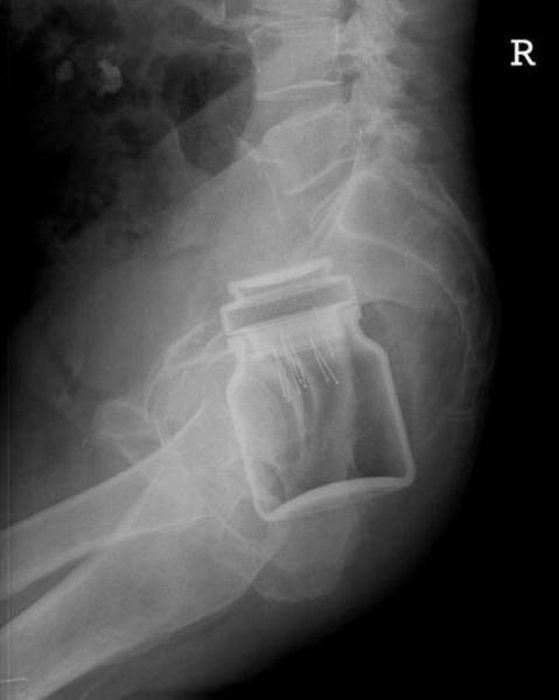

Предметы, которые не очень хочется видеть внутри себя

Под рентгеновскими лучами порой видны не только внутренние органы и кости, но и инородные тела, попавшие в организм

Истории попадания этих предметов в организм могут быть самыми невероятными и запутанными, но больше всего медиков интересует процесс их извлечения, впрочем, в этом заинтересованы и сами пациенты, допустившие нечто подобное со своим телом.